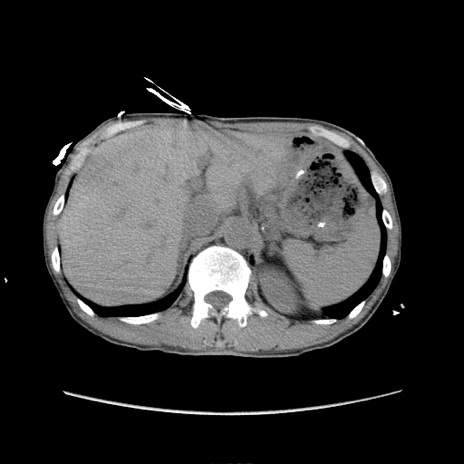

冠状断像

症例11(横断像)

【症例】 60歳代男性

【主訴】 下腹部痛

【現病歴】 本日夜中より下腹部痛の症状認め、受診。

【既往歴】 膀胱癌(膀胱全摘+尿管皮膚瘻術) 、胃癌術後

【身体所見】 BT 35.3℃、PR 58/min、BP 136/98mHg、腹部平坦、軟、腸蠕動音±、ストマ留置あり、左上腹部~正中部に圧痛あり、反跳痛なし。

【データ】WBC 5100、CRP0.01